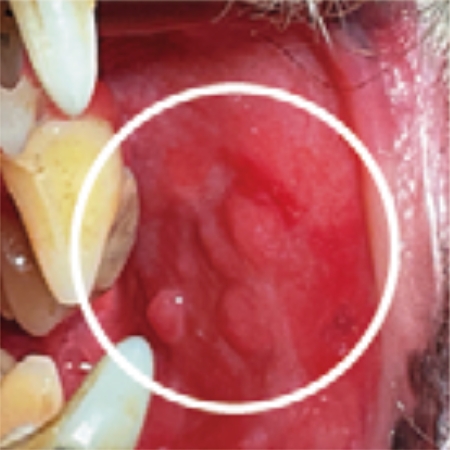

人と同じように、犬にも口内炎ができます。口の中の粘膜が炎症を起こし、赤くなったり、ただれたりするほか、出血したりします。犬では、進行した歯周病に続発して起きることが多いとされています。

口の中にあらわれる症状